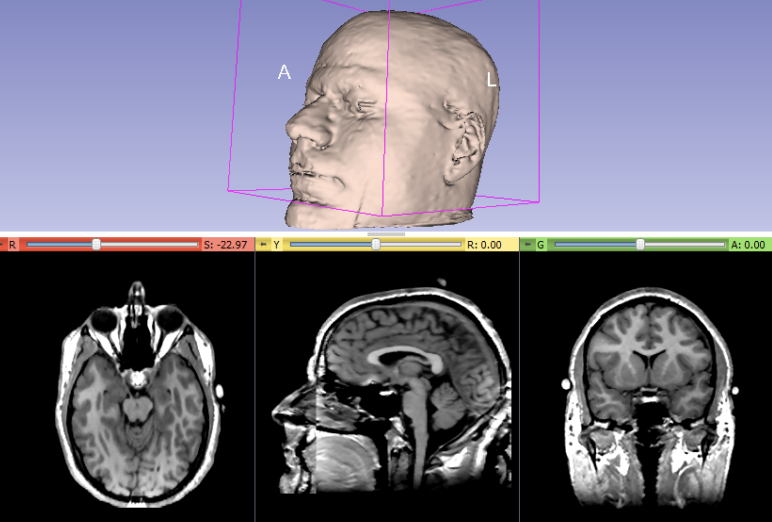

Image Volumes

Axial

Sagittal

Coronal

Voxel size for CT: 0.625-1.25 mm^3

similar to MRI